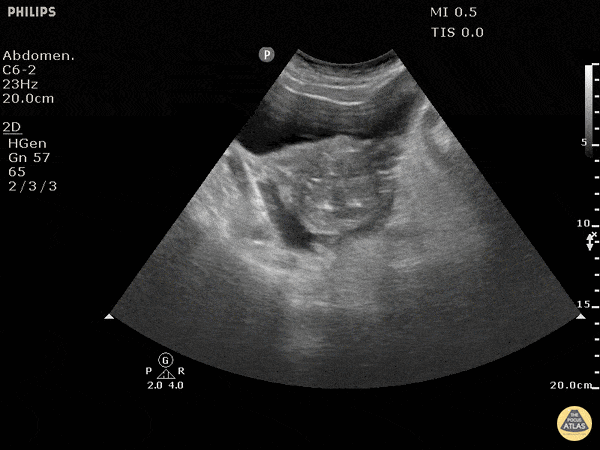

Sensitivity of 42% and specificity of ≥98% for peritoneal free fluid.

Whether the fast exam is used extensively or minimally, few will argue the utility of fast in the hypotensive trauma patient who is too unstable for ct in males, the seminal vesicles are occasionally mistaken for free fluid. Adjunct to traditional atls primary survey to enhance decision making around operative intervention in trauma. Free fluid usually occurs if a cyst ruptures (such as ovulation) or it leaks. This may be the intestines or any reproductive organ (ovary/uterus.) another cause of fluid includes trauma in the pelvic region.